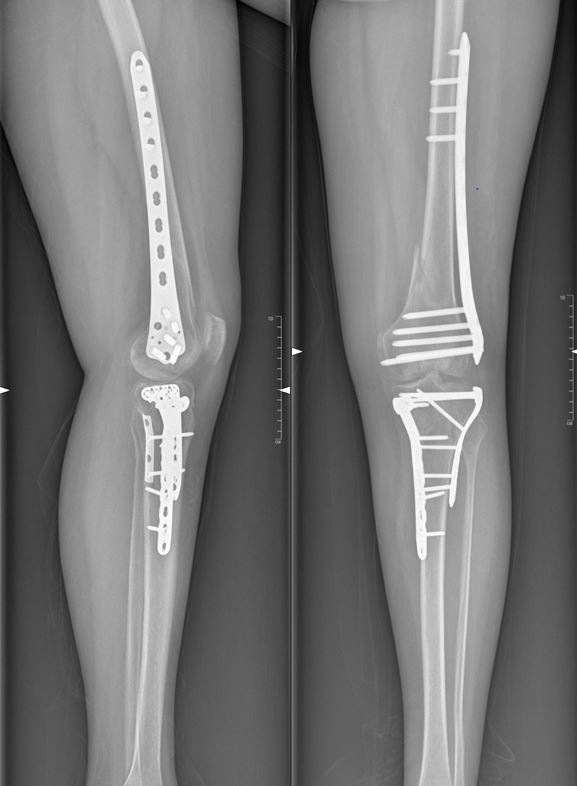

Примеры успешного применения ИИ в диагностике переломов

Мы собрали несколько примеров успешного применения ИИ в диагностике переломов, которые нас особенно впечатлили:

- В одной из больниц ИИ-система помогла выявить перелом запястья у пациента, который был пропущен врачом при первичном осмотре.

- В другой больнице ИИ-система значительно сократила время, необходимое для диагностики переломов, что позволило быстрее начать лечение пациентов.

- В отдаленном районе, где не было квалифицированного врача-рентгенолога, ИИ-система помогла выявить перелом ноги у ребенка, что позволило своевременно оказать ему медицинскую помощь.

Эти примеры демонстрируют огромный потенциал ИИ в улучшении качества медицинской помощи и спасении жизней.